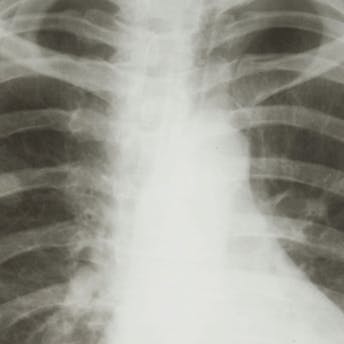

Overlev lungekræft … i Hovedstaden!

Det er langt fra ligegyldigt, hvor du bor henne, hvis du bliver ramt af alvorlig sygdom. I hvert fald ikke, hvis det er lungekræft, viser en detaljeret analyse af i rapporten 'Behandlingsindsats og relateret overlevelse ved lungecancer 2008 - 2010'. Rapporten gennemgår samtlige tilfælde af lungekræft, der er registreret i Dansk Lunge Cancer Register i perioden. Og der er tale om en stor, fælles arbejdsindsats. Rapporten er nemlig lavet i samarbejde mellem lungekræftlæger fra hele landet og er den mest omfattende og grundige af sin slags. Den gennemgår næsten 12.000 tilfælde af den meget alvorlige sygdom, der kræver hurtig behandling, hvis patienten skal overleve sygdommen. Og der er stor forskel mellem regionerne, skriver www.cancer.dk.

I Syddanmark, Midtjylland og Nordjylland er dødeligheden op til 20 procent højere end i Hovedstaden. Blandt andet fordi, der er forskel på, hvem der får tilbudt den mest effektive mulighed for helbredelse - nemlig operation, ligesom der også er forskel på, hvordan og hvornår de enkelte regioner bruger kemo- og strålebehandlingen, viser rapporten. Hovedstadens gode resultater skal selvfølgelig komme alle landets lungekræftpatienter til gode, og derfor skal sygehusledere i resten af landet sørge for at organisere deres indsats, så de når samme høje niveau, siger kræftens Bekæmpelses direktør, Leif Vestergaard Pedersen.